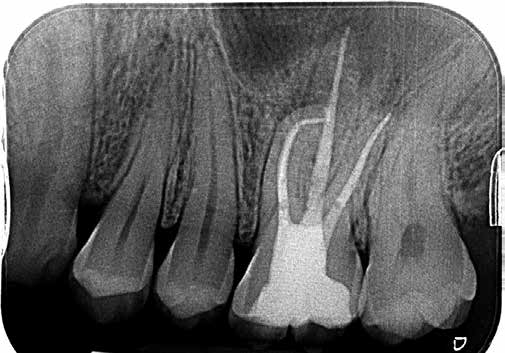

Nach der Aufbereitung wurden die Wurzelkanäle mit zum Feilensystem passenden Guttapercha-Mastercones (Conform Fit Technologie) bestückt. Ihr einwandfreier Sitz im Kanal ließ sich mithilfe einer Masterpointaufnahme kontrollieren (Abb. 8). Mithilfe warmvertikaler Kompaktion konnten die Wurzelkanäle danach gefüllt werden (Abb. 9). Aufschluss über die Passung dieser Füllung gab eine Backfill-Aufnahme (Abb. 10).

Der Blick auf das Röntgenbild zeigte eine suffiziente Füllung, sodass mit der Deckfüllung begonnen werden konnte.

Das klinische Endergebnis (Abb. 17) stellte den Patienten und mich als Behandler zufrieden. Auch die Röntgenkontrollaufnahme nach der Behandlung bestätigte den Erfolg (Abb. 18). Bei der Kontrolluntersuchung 1 Jahr nach der Behandlung stellte sich der Patient komplett beschwerdefrei in der Praxis vor. Die bei diesem Termin angefertigte Röntgenkontrollaufnahme ließ eine vollständige Remission der apikalen Aufhellung erkennen (Abb. 19).